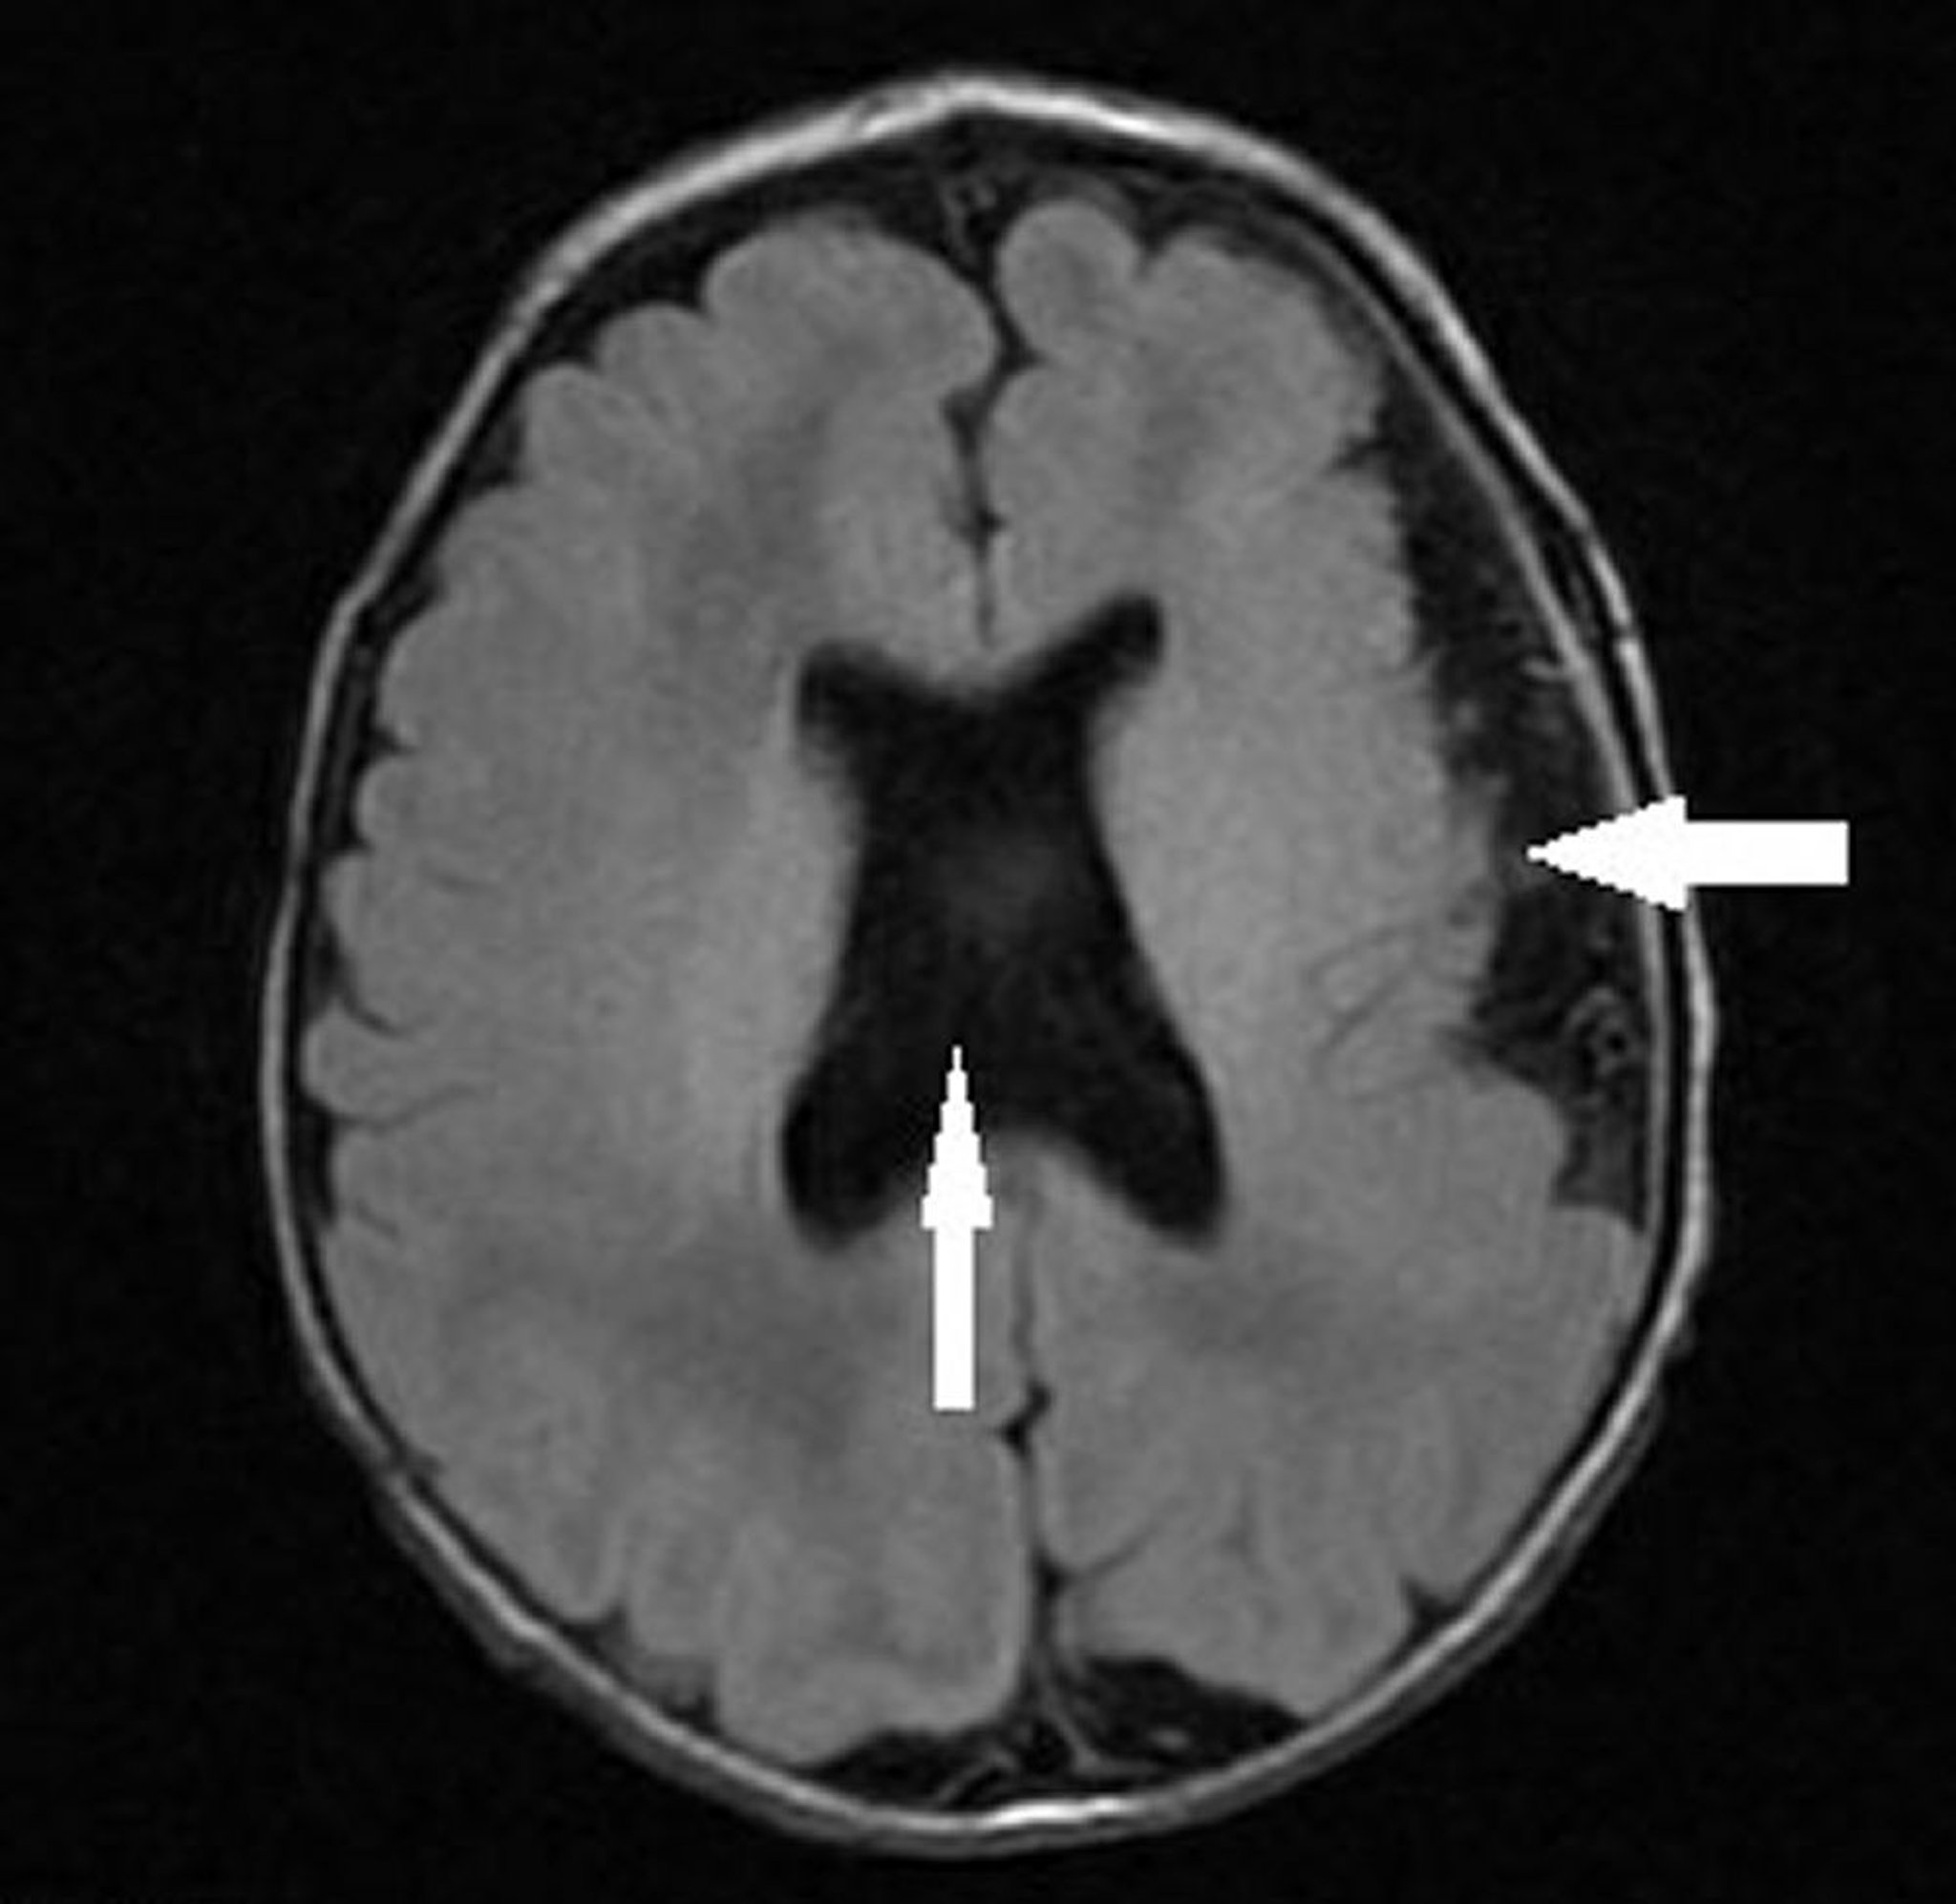

Polymicrogyria with Septo-Optic Dysplasia

This image shows an infant with left hemispheric polymicrogyria (leftward arrow) and absent septum pellucidum with abnormal ventricular configuration (vertical arrow) consistent with septo-optic dysplasia (optic nerve hypoplasia, absent or abnormal septum pellucidum, and pituitary hypoplasia).